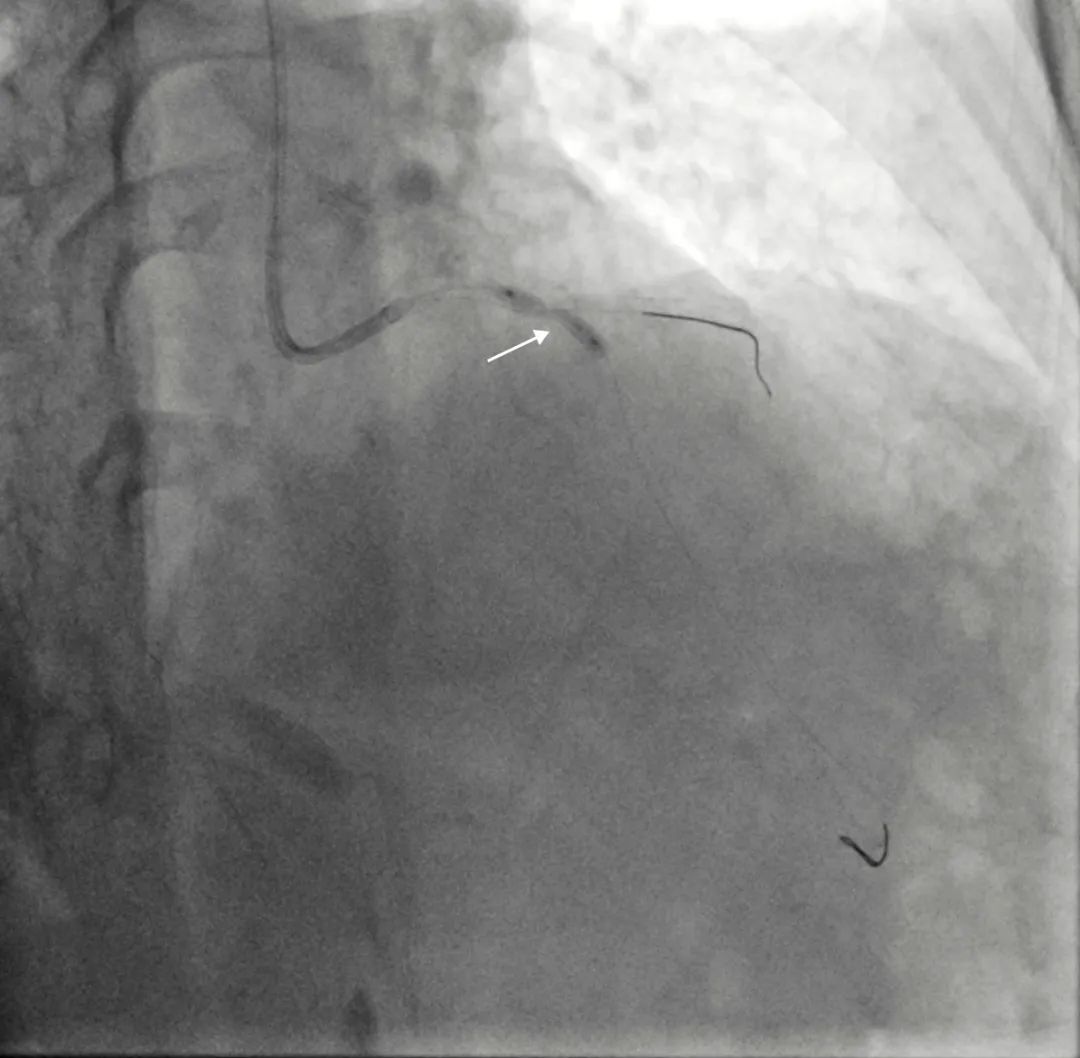

患者女,71岁,因“反复胸痛、胸闷4年余,加重”入院。患者入院诊断:冠心病不稳定心绞痛。入院完善相关检查后,患者2022年7月22日行冠脉造影提示:左主干无狭窄,前降支近段至中段90%狭窄伴钙化;回旋支近-中段弥漫性狭窄约70-90%;右冠近段至中段弥漫性狭窄约60-80%。拟对冠脉三支严重病变进行介入治疗。前降支近端至中段重度狭窄伴明显钙化。在使用2.5*15mm高压球囊,2.5*15mm切割球囊8-16atm反复预扩张后,仍无法充分扩张病变,考虑到前降支最重钙化病变处呈“小波浪”迂曲,行钙化病变旋磨术并发症风险较大,决定先完成左回旋支、右冠脉介入治疗后,择期再次对前降支严重钙化狭窄行介入治疗。

前降支造影:严重钙化狭窄病变处呈“小波浪”迂曲

前降支近段反复以高压球囊、切割球囊预扩张无法充分膨胀